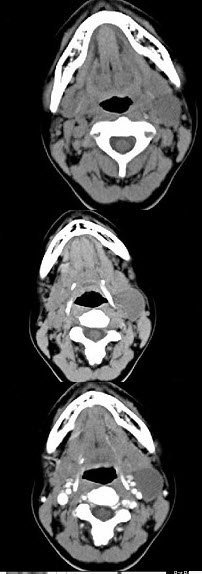

- 单项选择题女,16岁,发现左颈部肿块两年,CT如图所示,最可能的诊断为()。

D、左侧鳃裂囊肿

- D